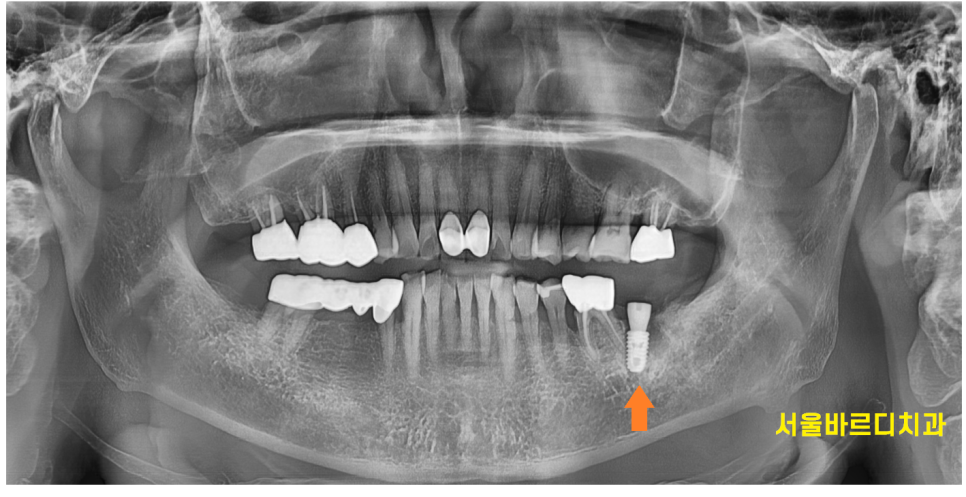

발치 후 천호동 치과에서 임플란트를 진행하기로 하였습니다.

주황색 부분이 웅덩이가 졌죠~?

뼈가 없는 부분입니다.

천호동 임플란트 직후 사진입니다.

당일에 이를 뽑고 임플란트를 심었습니다.

뼈가 부족한 부분은

임플란트 주변으로 뼈이식을 해드렸습니다.